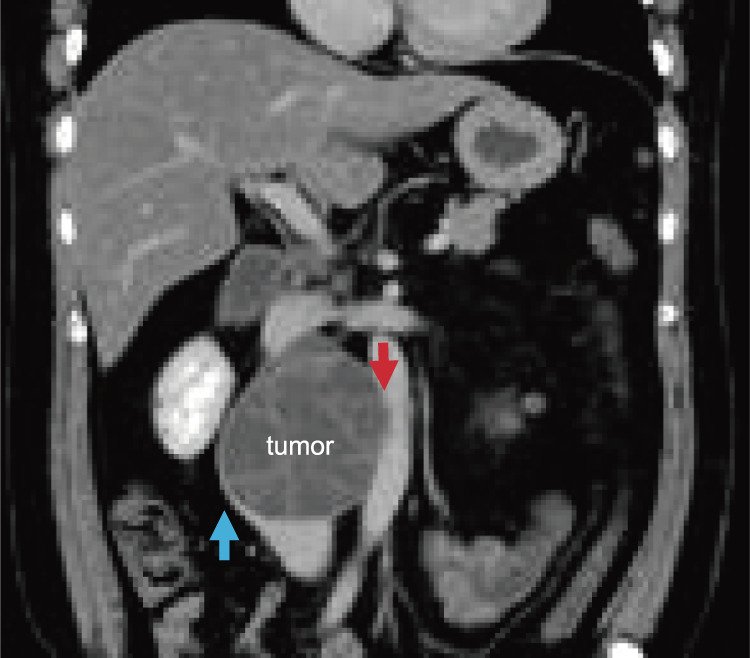

一名43岁的男子被诊断为腹膜后巨大肿瘤,疑似侵犯腹主动脉和下腔静脉,并接受了手术。通过横断和重建腹主动脉和下腔静脉,实现了肿瘤的全切。该病例强调,当主要血管受到侵犯时,需要积极、彻底地切除肿瘤。为确保全面切除肿瘤,尤其是在需要操作大血管的病例中,必须让心血管外科医生更多地参与此类手术。因此,广泛宣传肿瘤血管外科的概念至关重要。

A 43-year-old man diagnosed with a giant retroperitoneal tumor with suspected invasion of the abdominal aorta and inferior vena cava underwent surgery. Complete en bloc tumor resection could be achieved by transection and reconstruction of the abdominal aorta and inferior vena cava. This case highlights the need for aggressive, complete tumor resection when major vessels are invaded. To ensure comprehensive tumor removal, especially in cases requiring manipulation of major vessels, it is imperative to increase the involvement of cardiovascular surgeons in such surgeries. Therefore, widespread promotion of the concept of oncovascular surgery is essential.